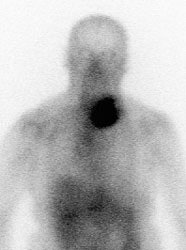

Non-Hodgkins Lymphoma: The Ga67 scan below was performed to evaluate for other sites of disease in a patient with a large non-Hodgkin's lymphoma in the left neck. Intense tracer uptake can be seen in the patient's tumor, but there were no other sites of disease identified. |